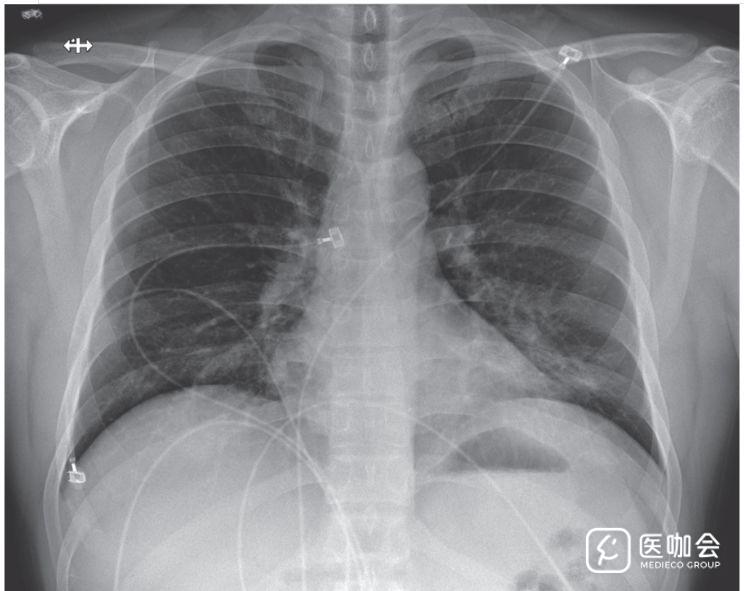

患者住院第3天(患病第7天)时,胸片仍未显示浸润或异常表现(图3)。但是,在住院第5天(患病第9天)晚上的胸片显示,左肺下叶有肺炎表现(图4)。

图4. 患者住院第5天(患病第9天)的胸片

影像学表现与患者住院第5天晚上开始的呼吸状态变化相吻合,当时患者未吸氧状态下血氧饱和度为90%。住院第6天时,患者开始吸氧。鉴于患者临床表现的变化,考虑到还有可能是医院获得性肺炎,开始对患者使用万古霉素(1750mg负荷剂量,之后每8小时静脉给药1g)和头孢吡肟(每8小时静脉给药一次)。

住院第6天(患病第10天),胸片显示两肺均有基底区条状阴影,与非典型肺炎相符(图5),且听诊时两肺均有啰音。

图5. 住院第6天(患病第10天)的胸片